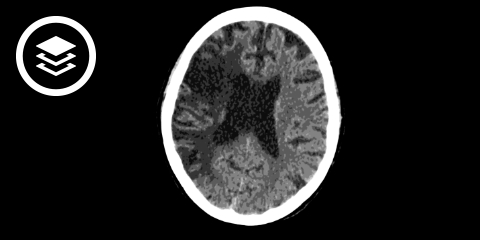

Computertomografie (CT)

Häufig wird beim Schlaganfall eine konventionelle CT des Schädels (CCT) durchgeführt. Hiermit kann man in der Akutphase unterscheiden, ob der Schlaganfall durch eine Blutung (hämorrhagisch, hyperdense Darstellung) oder durch einen Gefäßverschluss (Hirninfarkt) verursacht wurde. Dies ist von entscheidender Bedeutung für die weitere Therapie. Eine einfache konventionelle CT ohne Kontrastmittel ("native" CT, NECT) ist jedoch besonders in der Frühphase des Schlaganfalls nicht sehr sensitiv und ermöglicht keine genaue Einschätzung der Infarktausdehnung. Sollte jedoch bei entsprechender Klinik ein unilaterales hyperdenses Mediazeichen vorliegen ist von einem ischämischen Schlaganfall auszugehen.

Ergänzend werden deswegen zusätzlich zur konventionellen CT weitere speziellere CT-Untersuchungen zur Schlaganfall-Diagnostik eingesetzt:

- Perfusions-CT (PCT): Hiermit kann nicht nur erkannt werden, ob ein Schlaganfall vorliegt, sondern auch eine Unterscheidung zwischen irreversibel geschädigtem Hirngewebe (Infarktkern) und eventuell noch zu rettendem Hirngewebe (Penumbra bzw. "tissue at risk") durchgeführt werden (quantitative Durchblutungsmessung)

- CT-Angiographie (CTA): Zur Darstellung der Hirngefäße bzw. der Kollateraldurchblutung.

Durch die Kombination von NECT, PCT und CTA ("multimodale CT-Schlaganfall-Diagnostik") lassen sich deutlich mehr Informationen gewinnen, beispielsweise welches Gefäß verschlossen ist, und welcher Teil des Gehirns wie stark minderversorgt ist. Das erleichtert dem Behandler die Entscheidung über die initialen Therapiemaßnahmen und das weitere Vorgehen.

CT-Fallbeispiel